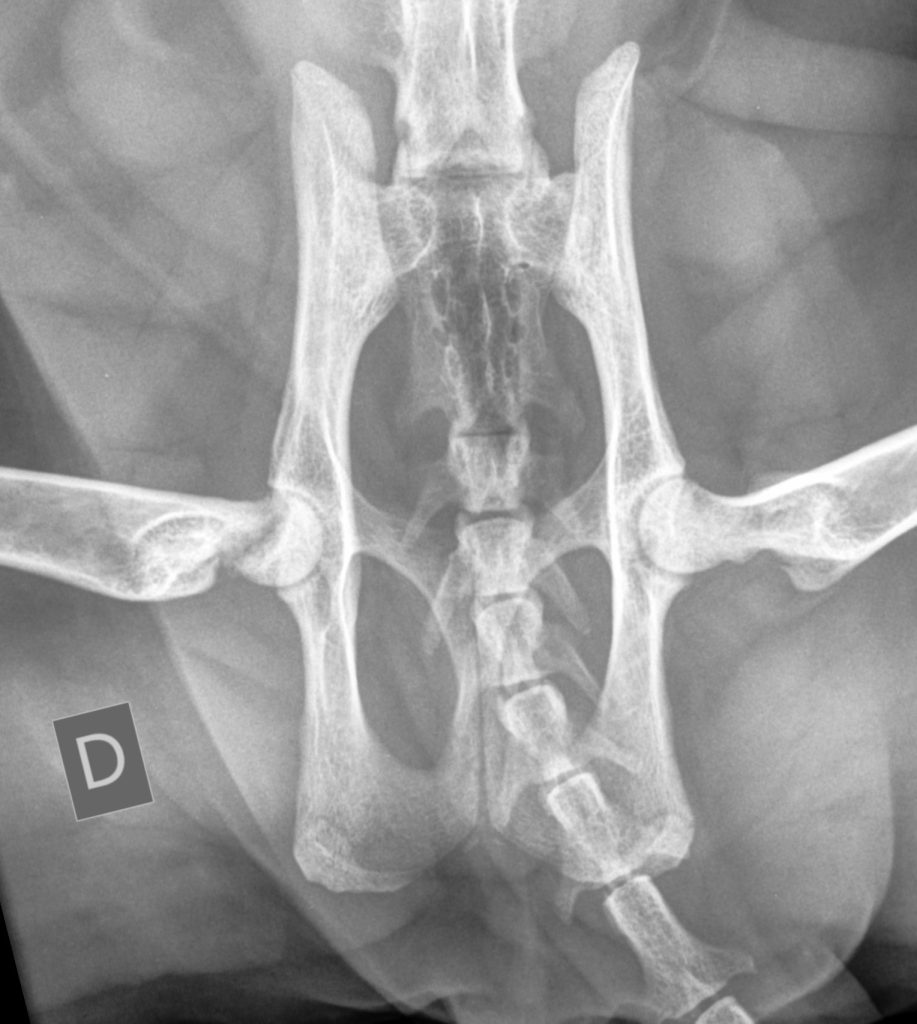

Le cas clinique de radiologie d'Alliance…

La santé articulaire est essentielle au bien-être des animaux de compa…

Le terme de « dysplasie » est un terme général qui pourrait êtr…